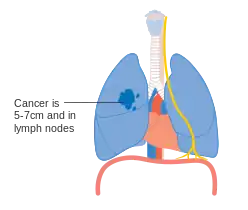

Lung cancer staging is an assessment of the degree of spread of the cancer from its original source.[77] It is one of the factors affecting both the prognosis and the potential treatment of lung cancer.[2][77]

The evaluation of non-small-cell lung carcinoma (NSCLC) staging uses the TNM classification (tumor, node, metastasis). This is based on the size of the primary tumor, lymph node involvement, and distant metastasis.[2]

Using the TNM descriptors, a group is assigned, ranging from occult cancer, through stages 0, IA (one-A), IB, IIA, IIB, IIIA, IIIB, and IV (four). This stage group assists with the choice of treatment and estimation of prognosis.[80]

- Diagrams of main features of staging

- Stage IIA lung cancer

- Stage IIB lung cancer

- One option for stage IIB lung cancer, with T2b; but if tumor is within 2 cm of the carina, this is stage 3

- Stage IIIA lung cancer

- Stage IIIA lung cancer, if there is one feature from the list on each side